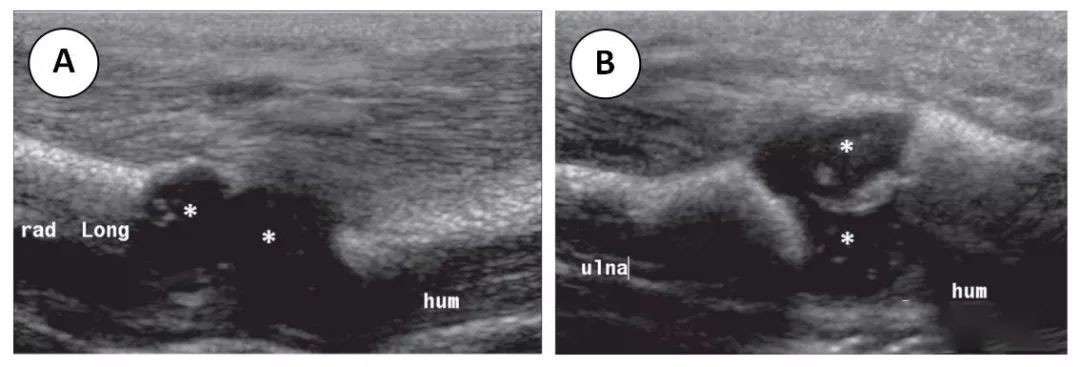

对于儿童,常规 X 线片是肘部成像的首选方式。计算机断层扫描,超声波检查 (美国) 和磁共振成像 (MRI) 可以进一步用来表征病理和解决问题。在创伤后行 CT 检查,以进一步确定复杂骨折的特征或用于制定手术计划。此外,CT 是一个很好的工具,它可以用来检查评估关节游离体,以及更好地发现皮质骨的细微裂隙或骨样骨瘤的微小病灶。与 CT 不同,US 避免了对儿童的辐射和镇静。超声是评估肘关节次生骨化中心的一种很好的成像方式。由于幼龄儿童次级骨化中心部分骨化或未骨化,超声可用于评估肘关节的协调性 (图 1)。最后,MRI 是评估骨髓、软骨结构或软组织异常的一种极好的成像方式。例如,当对存在肘关节积液但 X 线片上未见骨折线的患儿进行 MRI 检查时,发现约 57% 的患儿存在肘关节骨髓水肿,这表明在创伤后患儿存在隐匿性骨折。此外,MRI 在评估软骨结构 (如关节面和次级骨化中心)、骨组织损伤、骨软骨损伤和软组织损伤 (如韧带、肌腱和肌肉) 方面也有很好的效果。

图 1 4 天大的婴儿出生后手臂肿胀。x 线片提示尺近端骨折。考虑到肘部未骨化的骨化中心,以及对 Monteggia 骨折脱位的关注,我们对肘部进行了超声检查。两个纵向灰度超声图像显示 (A) 正常的肱桡关节和 (B) 正常的尺骨滑车关节。肘关节未骨化的软骨骨化中心 (星号) 清晰可见。